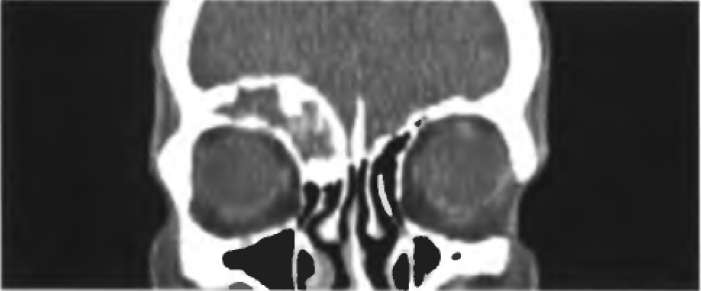

При компьютерной томографии в рентгеновских лучах (Рис. 3) изображения сечений объекта получают путем вычислений на основе рентгеновских исследований, выполненных во многих направлениях. Изображение анатомических структур получают посредством поперечных разрезов, свободных от ограничивающих применение рентгенографии влияний зферектов наложения. В настоящее время целые органы или части тела могут быть исследованы за короткие время, обычно меньше чем за 60 с. Получение такого объема инерормации посредством спиральной КТ (см. схему) позволяет воссоздать анатомические изображения с высоким уровнем прост­ранственного разрешения и в любой выбранной плоскости.

Рис 3. Изображения при компьютерной томографии (КТ) черепа в трех различных плоскостях, полученные техникой спиральной КТИзображения при компьютерной томографии (КТ) черепа в трех различных плоскостях, полученные техникой спиральной КТ